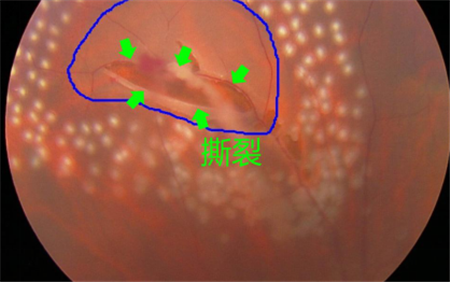

視網(wǎng)膜退化以及撕裂、后玻璃體脫落、葡萄膜炎、糖尿病或者黃斑變性引起的眼底出血等,可導(dǎo)致飛蚊癥產(chǎn)生,這種情況就屬于惡性飛蚊。雖然飛蚊本身并不會導(dǎo)致眼睛失明,但這些原發(fā)疾病若不及時治療,失明的風(fēng)險卻是非常大的。

所以在出現(xiàn)飛蚊癥時,建議上醫(yī)院做個檢查,看看屬于哪一種飛蚊。尤其是突然出現(xiàn)大量飛蚊、閃光,并伴隨視力下降或者視野缺損的情況,更需要及時就醫(yī)。在上海眼科醫(yī)院排名治療惡性飛蚊需要結(jié)合患者的原發(fā)疾病進(jìn)行治療,比如由視網(wǎng)膜裂孔導(dǎo)致的飛蚊癥,需要通過激光治療將裂孔封閉,從而避免視網(wǎng)膜進(jìn)一步脫落。